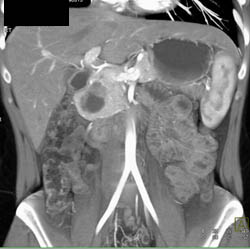

Diagnosis

Intraductal Papillary Mucinous Neoplasm (IPMN)